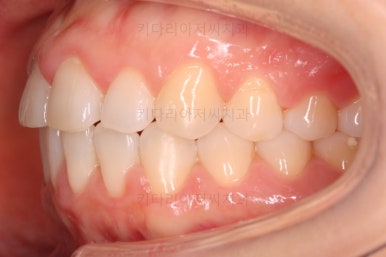

오늘 소개해 드릴 환자분은 앞니가 나비 날개처럼 꺾인 양상으로 틀어져 있었던 분으로 부분교정을 통해 개선을 하고자 하셨던 분입니다.

부산나비앞니교정 키다리아저씨치과에 처음 내원하셨을 당시의 입 안 모습입ㄴ디ㅏ.

보시다시피 위아래 정중앙에 있는 치아가 V자 형태로 꺾여있었어요.

흔히 "나비치아", "나비앞니"라고 표현을 하는데 나비 날개짓을 하듯이 꺾여 있다고 그렇게 부릅니다.

어금니쪽의 맞물림은 굉장히 양호한 편이였기 때문에 부분교정에 딱 알맞는 경우였어요.